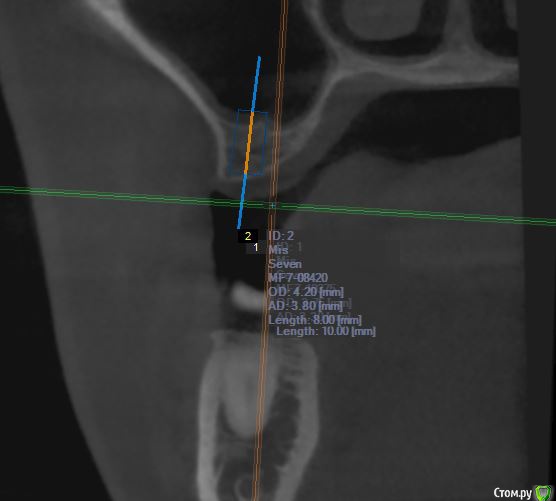

jm3300 Опубликовано 12 июля, 2016 Автор Поделиться Опубликовано 12 июля, 2016 А до операции КТ могли бы выложить? И сколько времени отсутствовали зубы в этой области?отсутствовали достаточно долги. КТ до: Ссылка на комментарий

jm3300 Опубликовано 14 июля, 2016 Автор Поделиться Опубликовано 14 июля, 2016 выкладываю кт Ссылка на комментарий

умножающий печаль Опубликовано 14 июля, 2016 Поделиться Опубликовано 14 июля, 2016 Промыть пазуху через соустье, курсом. Я отправляю к ЛОРам. Антибиотикотерапия, гипосенсибилизация. Один из винтов вестибулярно без костной поддержки, на мой взгляд. 1 Ссылка на комментарий

red_butler Опубликовано 15 июля, 2016 Поделиться Опубликовано 15 июля, 2016 гайморит всё таки есть?Не увидел, один винт похоже на выход 1 Ссылка на комментарий

red_butler Опубликовано 15 июля, 2016 Поделиться Опубликовано 15 июля, 2016 Пазуха чистая, Антон, какой винт на выход не понял?Может у пац аллергия ?На последних срезах, вестибулярно на 2/3 кости нет.Какая уж аллергия, если боль и отек 1 Ссылка на комментарий

умножающий печаль Опубликовано 15 июля, 2016 Поделиться Опубликовано 15 июля, 2016 Тоже не понял, вроде все хорошо стоят. Главное слизистые то в покое.Это пока в покое. Винт не покрытый костью, долго под мягкими тканями оставаться не будет. Неизбежна рецессия со всеми вытекающими. 1 Ссылка на комментарий